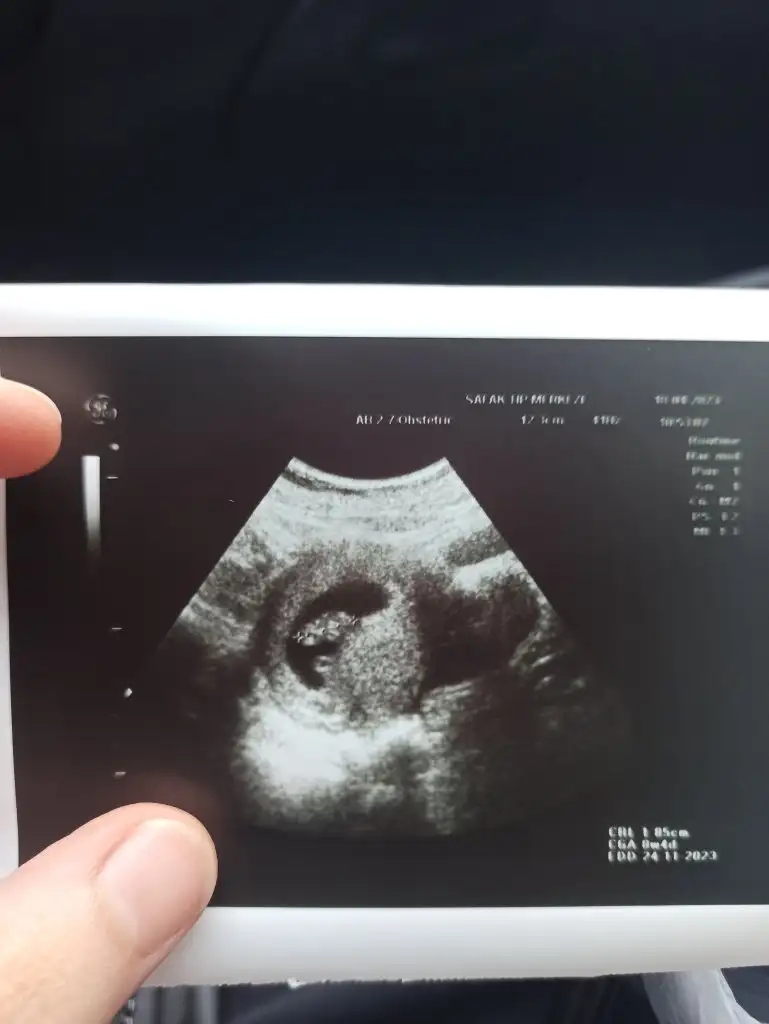

1ciftyesilgozz merhaba kizlar 8 haftalik olduk dun doktora gittik iki oglumdan sonra fikirlerinizi alayim varmi bizede bir tahmin

Eklentiler

• ED29E629-549D-4E18-9554-8B8E59BB173E.webp

16 KB · Görüntüleme: 70

• 2EB25C88-F3C3-4BF4-A081-754B702961A4.webp

94,6 KB · Görüntüleme: 56

• 76529EE5-2145-4C63-8B1D-C3103B91523A.webp

106,6 KB · Görüntüleme: 56